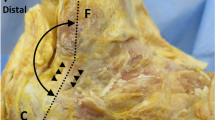

All ultrasounds were bilateral according to a standardized protocol using the Aixplorer machine (SuperSonic Imagine, Aix-En-Provence, France) equipped with a 12-MHz superficial linear transducer. Patients were placed in a prone position, with legs extended. The examination began with grayscale B mode and power Doppler ultrasound to eliminate any signs of tendinopathy. The width (mm) and thickness (mm) of each tendon were measured with axial (i.e., perpendicular to the direction of the fibers) grayscale ultrasound 5 cm from the end of the tendon. The cross-sectional area (mm2) of each tendon was calculated using the following formula: cross-sectional area = π × width/2 × thickness/2. Measurements in elastographic mode were made successively for four passively mobilized ankle positions: position no. 1: maximal plantar flexion; position no. 2: 45° plantar flexion; position no. 3: 0° flexion; position no. 4: 45° dorsiflexion or maximal dorsiflexion for patients who did not sustain 45° dorsiflexion (Fig. 1). The mean shear wave velocity (Vmean, m.s−1) was measured in elastographic mode (SWE) by placing a region of interest (ROI) with the following requirements: constant round size (3 mm in diameter) situated in the center of the tendon 5 cm from its end, both in sagittal (i.e., parallel to the direction of the fibers) and in axial SWE (Fig. 2). Young’s modulus Emean (kPa) was calculated from Emean = 3 ρVmean 2[13] where density ρ is assumed to be constant (1,000 kg.m−3), under the assumption of a purely elastic model. Standard deviation of the ROI was used as an estimate of the quality of the measurement: standard deviation of shear wave velocity (VSD) and the standard deviation of Young’s modulus (ESD) within the ROI were also measured. The relative anisotropy coefficient (A) was calculated using the following formula: A = (sagittal Vmean – axial Vmean)/sagittal Vmean.

Calcaneal tendon was examined at 5 cm from the end of the tendon consecutively for four degrees of ankle flexion. Position no. 1: maximal plantar flexion; position no. 2: 45° plantar flexion; position no. 3: 0° flexion; position no. 4: 45° dorsiflexion. As it may have increased tissue stiffness, pre-compression was avoided by interposition of a gel pad between the probe and the skin. The position was maintained and controlled by fastening feet on an articulated board

The calcaneal tendon has tendinous fibers that lie parallel to each other. There is therefore an axis of symmetry along the fibers that relates to a hexagonal system (transverse isotropy) according to the viscoelasticity theory [28]; This enables to define two main axes: one parallel and one perpendicular to the fibers. The small difference in the mean values of Young’s modulus along the direction perpendicular to the fiber axis (E11 and E22, Fig. 3) measured by Kuo [29] seems to confirm the transverse isotropy model. In a study of muscle elastography, Gennisson [30] showed that shear wave velocity is a function of the angle between the transducer and the main axis of the muscle fibers. Maximum velocity is reached when the transducer is parallel to the fibers and minimum velocity when the transducer is perpendicular to the fibers. Our results on the calcaneal tendon are similar, and we estimate the relative anisotropy coefficient A of the calcaneal tendon at rest at 0.24 ± 0.16. This confirms that, much like muscle, normal tendon is anisotropic, and that the orientation of the transducer axis in relation to the tendon fiber axis must be known in order to accurately interpret the quantitative values provided by the device. Anisotropy is almost three times higher for a stretched tendon (position no. 3) than at rest (position no. 1). This result is consistent with previous work on muscle anisotropy [30].